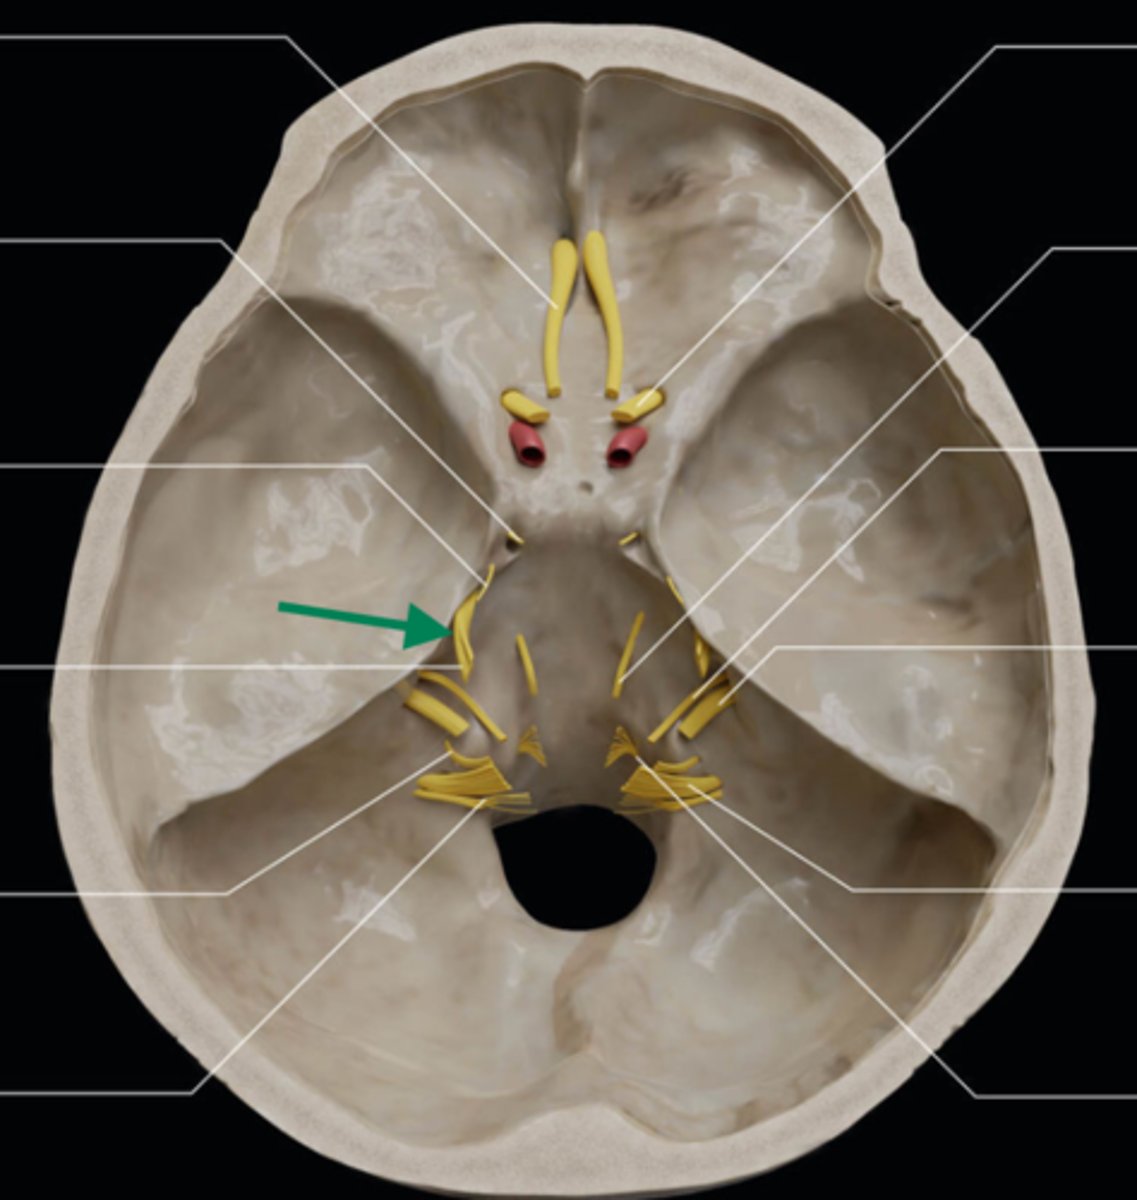

olfactory bulb

olfactory tract

optic nerve (CN II)

internal carotid artery

oculomotor nerve (CN III)

trochlear nerve (CN IV)

abducent nerve (CN VI)

trigeminal nerve (CN V)

facial nerve (CN VII)

vestibulocochlear nerve (CN VIII)

glossopharyngeal nerve (CN IX)

vagus nerve (CN X)

accessory nerve (CN XI)

hypoglossal nerve (CN XII)

optic chiasm

trigeminal ganglion

anterior cranial fossa